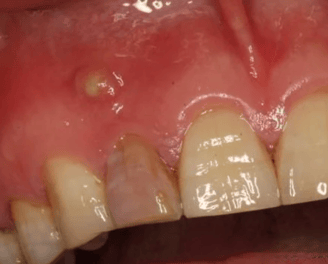

Se trata infecciones o abscesos que se forman en el tejido alrededor de la raíz del diente. Este tratamiento busca eliminar la infección y preservar el diente

Tratamiento de lesiones periapicales

Tratamiento de abscesos dentales

Se trata de una infección en el extremo de la raíz del diente que forma una acumulación de pus. El tratamiento incluye la limpieza y desinfección del conducto radicular y, en algunos casos, el drenaje del absceso.

Tratamiento de Absceso Periapical

Es una inflamación crónica en el extremo de la raíz del diente que forma una masa de tejido. El tratamiento incluye la eliminación del tejido infectado mediante un tratamiento de conducto y, en casos severos, cirugía apical

Tratamiento de Granuloma Apical